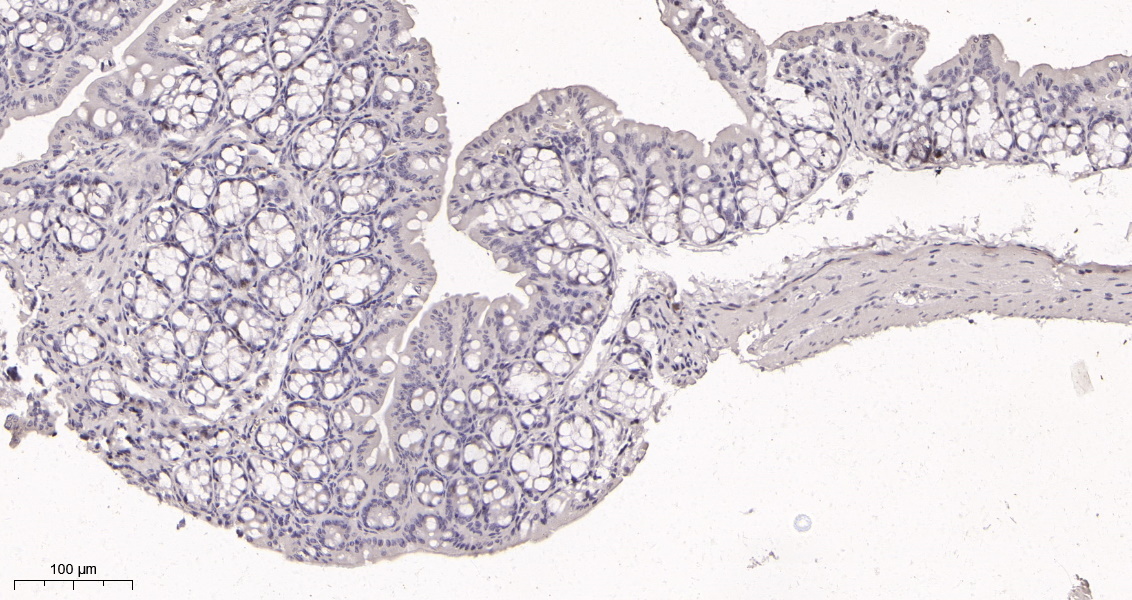

货号IM68914

别名MKI67;Antigen KI-67

产品名称Ki67 (16S9) Rabbit Monoclonal Antibody

推荐应用WB,IHC-P,IF-P,IF-F,IF-ICC,ELISA

反应种属Human,Mouse,Rat

稀释度IHC-P 1:200-1000,WB 1:1000-5000,IF-P/IF-F/IF-ICC 1:200-1000,ELISA 1:5000-20000,IP 1:50-200

参考分子量359kDa

背景介绍This gene encodes a nuclear protein that is associated with and may be necessary for cellular proliferation. Alternatively spliced transcript variants have been described. A related pseudogene exists on chromosome X. [provided by RefSeq, Mar 2009],

功能developmental stage:Expression of this antigen occurs preferentially during late G1, S, G2 and M phases of the cell cycle, while in cells in G0 phase the antigen cannot be detected.,function:Thought to be required for maintaining cell proliferation.,online information:Ki-67 entry,similarity:Contains 1 FHA domain.,subcellular location:Predominantly localized in the G1 phase in the perinucleolar region, in the later phases it is also detected throughout the nuclear interior, being predominantly localized in the nuclear matrix. In mitosis, it is present on all chromosomes.,subunit:Interacts with KIF15. Binds through the FHA domain to MKI67IP.,